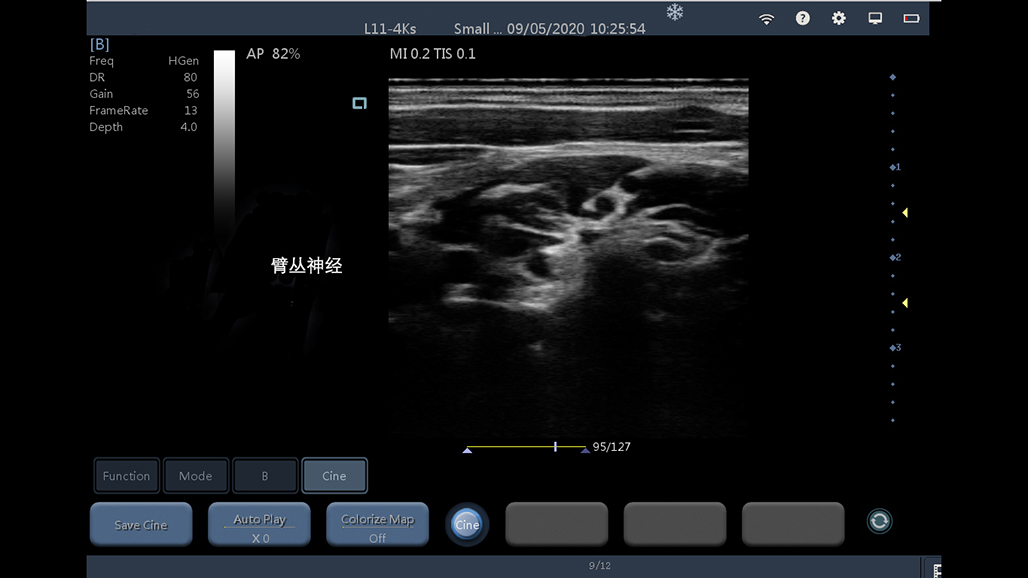

• 线阵

甲状腺

血管

神经

肌骨等